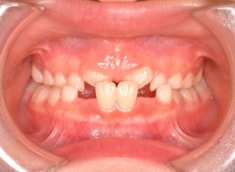

治療前

歯牙の大きさ(マテリアル)分析:偏差値55.2なので、歯のサイズは平均よりは大きめです

日本人の典型的なパターンである、上顎劣成長が顕著で、下顎骨体自体も大きい値を示しています。

Facial Axis(顔の成長方向):95.8°なので、今後下顎前突傾向は旺盛であると予測されます。